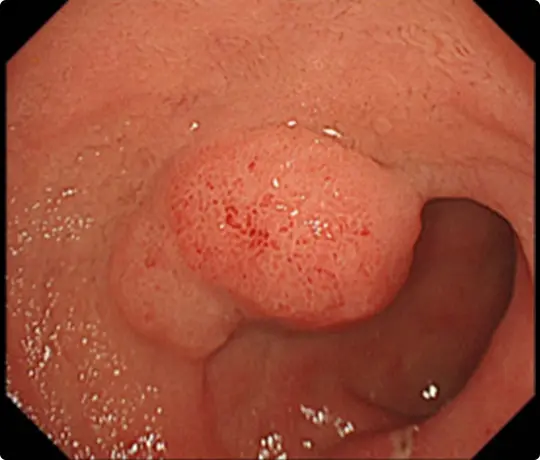

約25mmの十二指腸腫瘍を認めます。